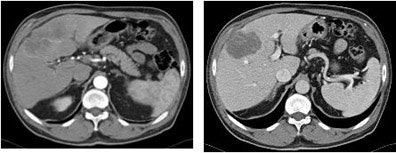

| Using high-concentration contrast, medium tumor-feeding vessels and a hypervascularized rim of the carcinoma were depicted in arterial-phase images (left). Venous phase (right) demonstrated a hypodense lesion with moderate enhancement of the periphery. Inner vascular perfusion was visualized to a high degree. Images courtesy of Dr. Renate Hammerstingl. |

"Here, an example of a patient suffering from cholangiocarcinomas," she said displaying a slide. "Note that the feeder tumor is excellently depicted in arterial-phase imaging, as well as peripheral enhancement using the high concentration, and using thinner sections, the inner architecture of the tumor is well depicted."